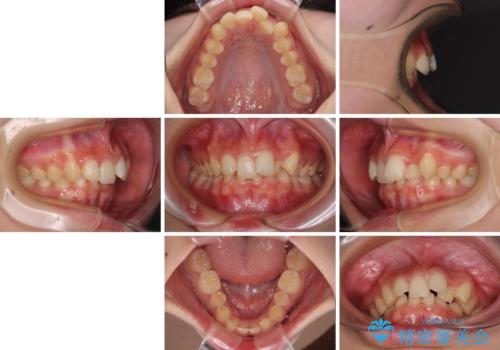

- 下顎前歯が欠損しており、前歯がデコボコとなっている歯並びを気にして来院された患者様です。

下顎の左右側切歯2本が欠損しており、上顎歯列がデコボコとなっている状態でした。

下顎歯列に対して上顎歯列が相対的に大きくなっているため、デコボコとなっているだけでなく、下顎前歯が見えなくなるくらいのディープバイトにもなっていました。